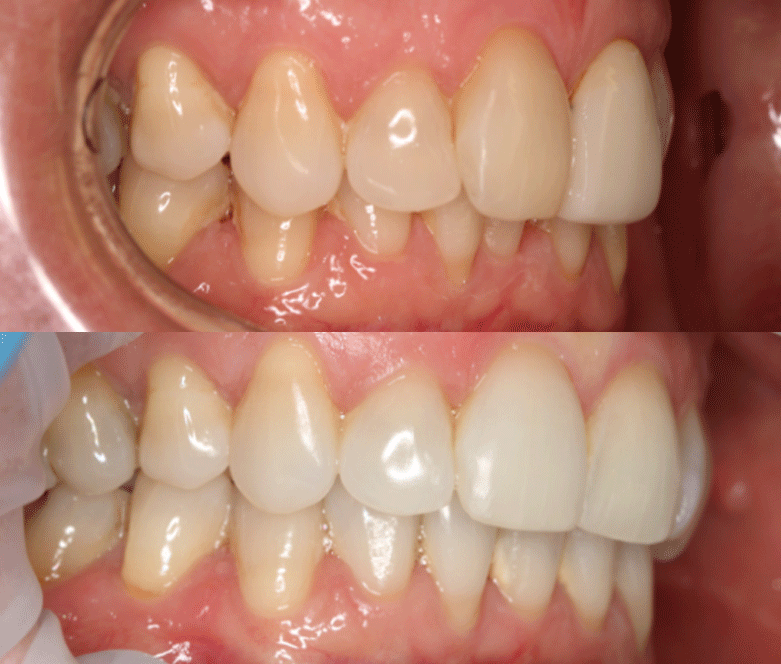

We will then map out a complete treatment plan showing the gradual realignment that will reposition the teeth from their current position to where they will be when the treatment is complete.